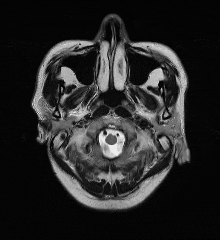

02、术前影像

头颅MR未见明显病灶。

1. 锁骨下动脉闭塞(左侧,伴盗血)

右侧椎动脉造影提示左侧锁骨下动脉盗血,左侧锁骨下动脉闭塞,近端残端较圆钝。